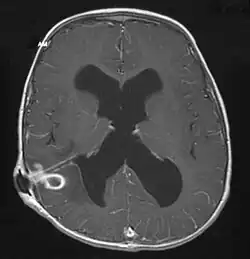

| Brain abscess in a person with a CSF shunt. The abscess is the darker gray region in the lower left of the image (corresponding to the right parietal lobe). The lateral ventricles are visible in black in the center of the brain, adjacent to the abscess.[1] | |